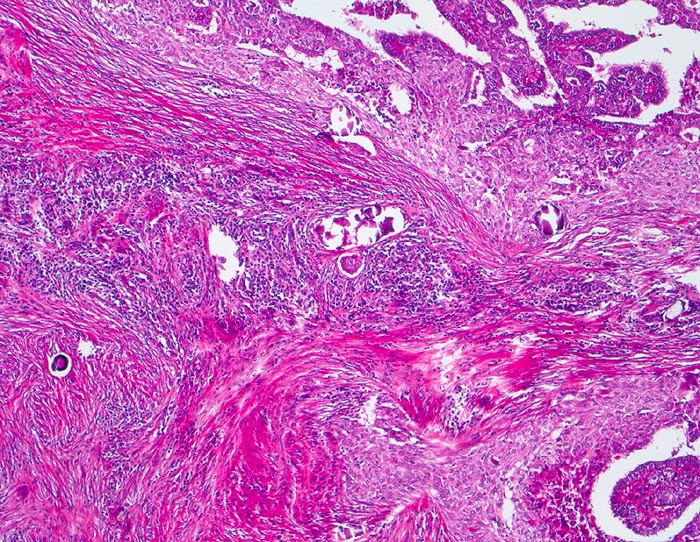

Infiltration der Schilddrüse durch ein papilläres Karzinom mit teils epidermoider Architektur. Auffällige Stromasklerose mit lymphozytärem Entzündungsinfiltrat. Zahlreiche Psammomkörperchen.

Das diffus sklerosierende papilläre Karzinom ist gekennzeichnet durch eine diffuse Infiltration der gesamten Schilddrüse mit Lymphangiosis carcinomatosa begleitet von einer deutlichen Sklerose und chronischen Entzündung. Dieser Tumortyp tritt bevorzugt bei jüngeren Patienten auf und hat eine schlechte Prognose. Plattenepithelmetaplasien treten in bis zu 7% der Schilddrüsenkarzinome auf.